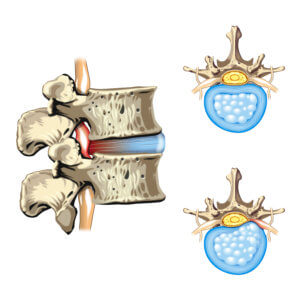

椎間盤( 軟骨) 在上下兩節脊椎骨之間,由內層的骨髓核( 啫喱狀物) 及外層的纖維環所構成。椎間盤的作用是吸收脊椎所承受的壓力,亦有避震的作用,當我們擺動身體,向前或向後彎腰時, 軟骨亦同時作出不同的形狀來配合身體的動作。但隨著年齝增長及長期身體負重,到了三十歲左右, 髓核會開始脫水和變質,吸收壓力的能力亦會降低,同時纖維環也開始出現退化。當我們不覺地做 出一些不當的姿勢或動作,便可能造成椎間盤 ( 軟骨 ) 突出。

上圖椎間盤沒有突出、而下圖椎間盤有突出